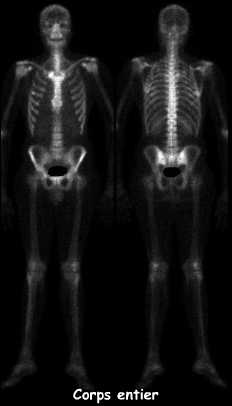

La scintigraphie corps entier a montré une hyperfixation franche se projetant en regard de l'articulation sterno-claviculaire droite.

Par ailleurs, il existe un foyer d'hyperfixation au niveau de l'arc axillaire de la 5ème côte droite.

Il n'existe pas d'autre anomalie osseuse d'allure évolutive.